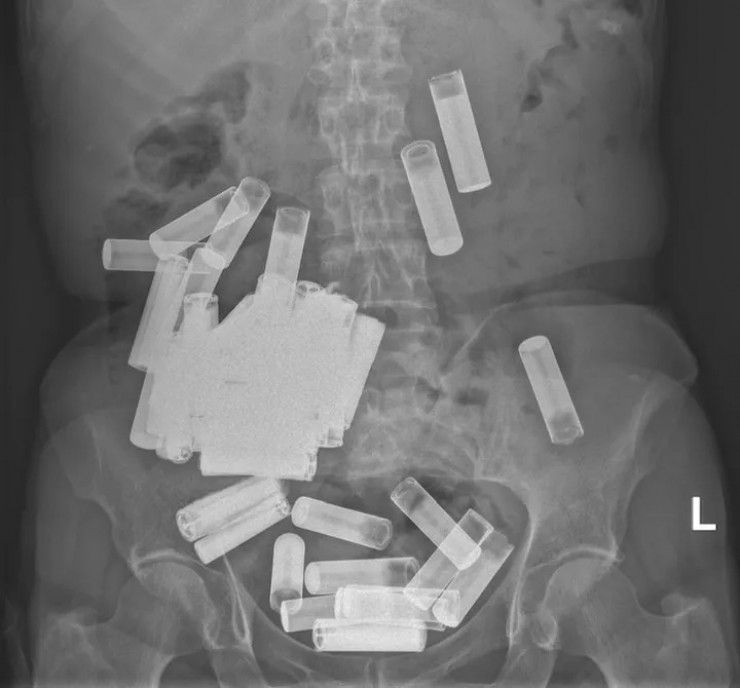

В Ирландии врачи извлекли у женщины из желудка 55 батареек

В Ирландии врачи вытащили из желудка и толстой кишки 66-летней пациентки 55 пальчиковых батареек.

Жительница Дублина обратилась в госпиталь Святого Винсента с жалобами на вздутие живота и боли, передает Tengrinews.kz со ссылкой на HuffPost.

Медики сделали УЗИ и обнаружили в ее желудке и толстой кишке массу посторонних предметов.

Сначала медики решили подождать, пока инородные предметы выйдут из организма естественным путем, но спустя неделю тело покинули всего пять батареек, а боль в животе пациентки усилилась. Тогда врачи решили прооперировать женщину и извлекли из нее еще 50 пальчиковых батареек.

— Насколько нам известно, этот случай представляет собой самое большое зарегистрированное количество батареек, проглоченных в один момент времени — говорится в статье.

На данный момент пациентка находится под наблюдением врачей. О том, как такое количество батареек оказалось внутри женщины, не сообщается. Однако врачи отметили, что проглатывание батареек является весьма опасным способом членовредительства, так как может вызвать серьезные проблемы, включая повреждение слизистой оболочки, перфорацию и обструкцию.